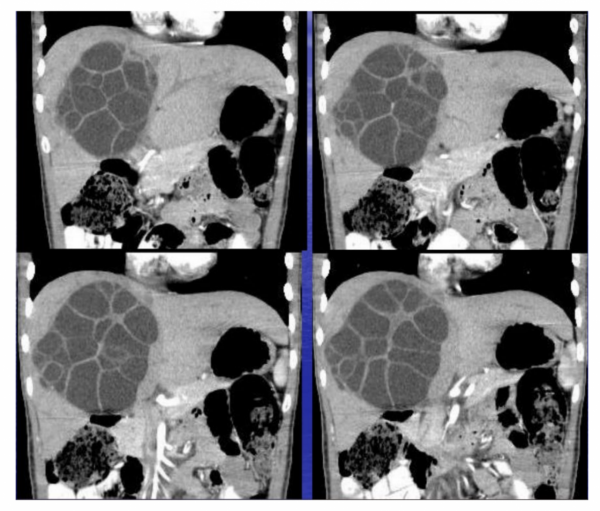

新聞則報道:20歲的女孩,她叫劉迪,兩年前,因面板乾燥發黃伴隨著間斷性腹痛,後去醫院就診,被診斷出肝臟內可能存在寄生蟲,從根源處理掉病灶,最好立即進行手術治療。可成績優異的她不想耽誤學業而放棄了治療。如今已經大二的她,再次出現皮膚髮黃暗淡以及腹痛,眼睛也開始發黃,還伴隨著肝臟的劇烈疼痛。嚴重時會陷入了一度昏厥。家人感覺到嚴重性,立即帶著劉迪去了當地拉薩市人民醫院進行就診,醫生在問診後立即讓其做了全面檢查。經檢查CT提示:肝臟內的實性腫塊,其右側肝佔位,直徑達15cmx18cm,且內囊存在寄生蟲。隨即,醫生很清晰地診斷為“肝包蟲病”。

肝包蟲病被稱為“蟲癌”,是一種極少見但嚴重的寄生蟲病,其致病性強,致殘率和致死率高。在免疫功能正常的患者中,肝包蟲感染可以10-15年都不會出現感染。肝包蟲主要侵犯肝臟,感染可區域性擴散或透過血管轉移至其他器官,肺是最常見的轉移部位。臨床上,感染後可出現假腫瘤性肝腫大、梗阻性黃疸、膽管炎、門靜脈高壓症、加布綜合徵等表現;在合併肺轉移後,患者可出現胸痛、咳嗽、咯血等症狀;在合併腦轉移,患者可出現癲癇、顱內高壓或各類麻痺等症狀。患者最終因肝功能衰竭、膽系感染以及肺、腦等器官轉移而致死亡。